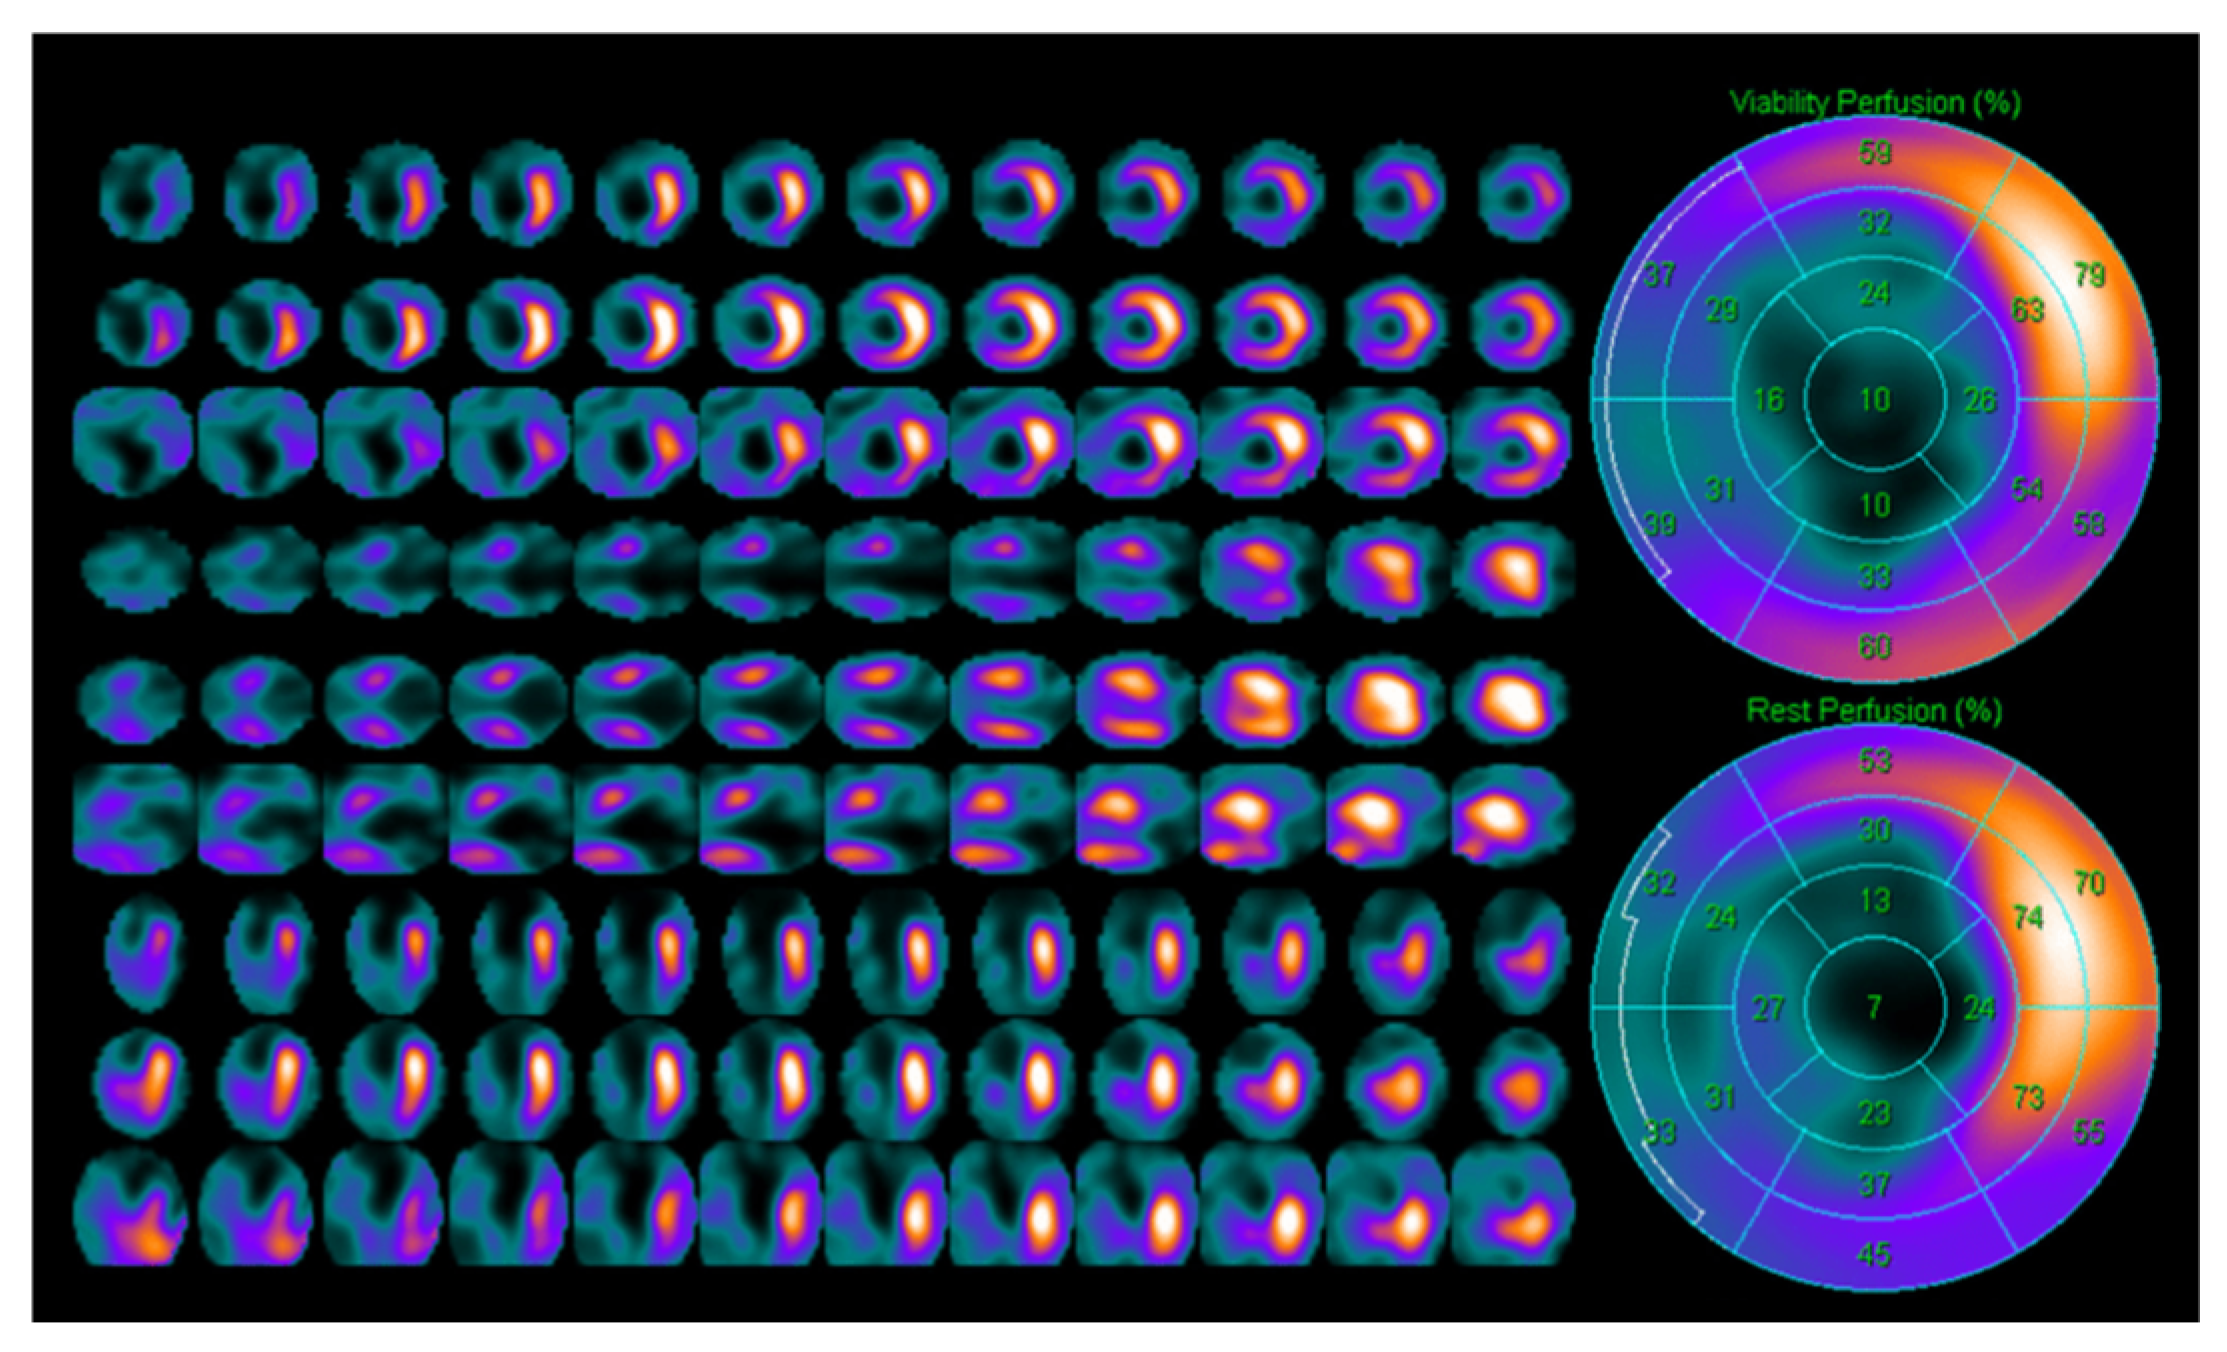

4. Positron Emission Tomography (PET Scan)

5. Single Photon Emission Computed Tomography (SPECT)